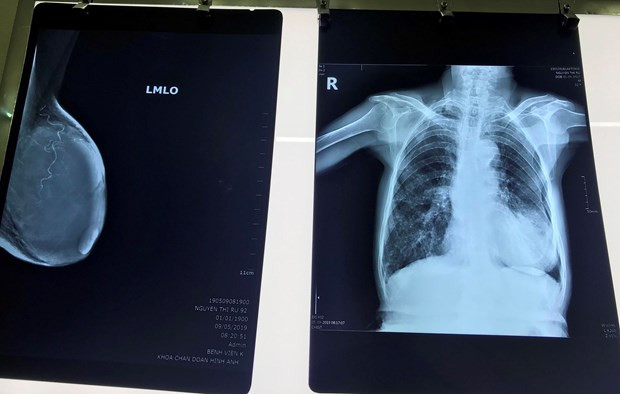

| Phim chụp khối u của bệnh nhân. (Ảnh: PV/Vietnam+) |

Sau khi các bác sỹ thăm khám, chụp chiếu, kết quả cho thấy khối u kích thước 10x6cm chiếm toàn bộ vú trái bệnh nhân, được chẩn đoán ung thư vú giai đoạn tiến triển.